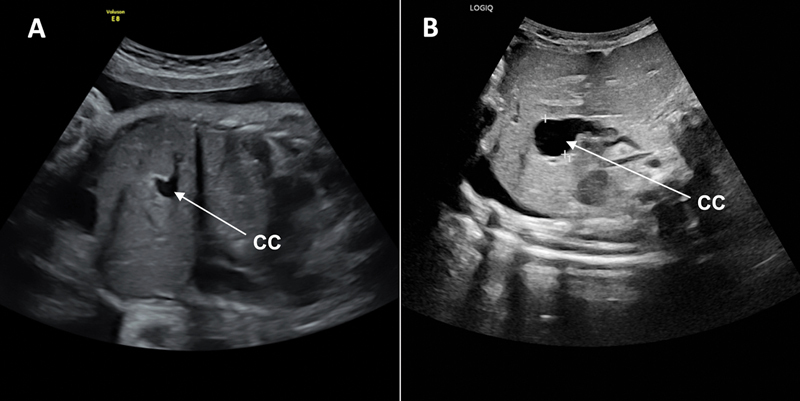

Patients with congenital diaphragmatic hernia (CDH) can present with other congenital anomalies, but an associated choledochal cyst (CC) has rarely been described. The simultaneous diagnosis of both anomalies complicates patient management. There is no consensus on the ideal timing for CC excision. Unrepaired CC is associated with risks of developing biliary sludge, choledocholithiasis, and cholangitis. After a CDH repair with mesh, secondary bacterial translocation caused by a delayed CC repair could lead to mesh superinfection. Conversely, early CC surgical management could cause mesh displacement and lead to CDH recurrence, requiring reintervention. We present the rare case of a CC occurring in a neonate with a prenatally diagnosed right CDH. One month after an uncomplicated CDH repair with mesh, while the patient was still hospitalized for pulmonary hypertension, she developed progressive cholestasis and acholic stools. Investigations revealed a nonpreviously suspected CC. Conservative treatment was attempted, but CC perforation with secondary biliary peritonitis occurred. Open CC excision with a Roux-en-Y hepaticojejunostomy was therefore performed on day of life (DOL) 41. Having suffered no short-term surgical complications, the patient was discharged on DOL 83 because of prolonged ventilatory support due to pulmonary hypertension. Now 12 months after surgery, she is doing well with normal liver function tests and imaging studies. In summary, CC should be considered in the differential diagnosis of progressive cholestasis in patients with CDH. Surgical repair of a symptomatic CC should not be delayed even in the presence of mesh given the risks of CC complications.

先天性膈疝(CDH)患者可能伴有其他先天性畸形,但伴有胆总管囊肿(CC)的病例却很少见。同时诊断出这两种畸形会使患者的治疗变得复杂。关于切除 CC 的理想时机,目前还没有达成共识。未修复的CC有发展成胆汁淤积、胆总管结石和胆管炎的风险。在使用网片进行CDH修复后,延迟CC修复引起的继发性细菌易位可能导致网片超级感染。反之,过早进行CC手术治疗可能会导致网片移位,导致CDH复发,需要重新进行手术治疗。我们介绍了一例产前确诊为右侧 CDH 的新生儿发生 CC 的罕见病例。在使用网片进行无并发症的CDH修补术一个月后,患者因肺动脉高压仍在住院治疗,但出现了进行性胆汁淤积和大便隐痛。检查结果显示她患有之前未被怀疑的CC。医生尝试了保守治疗,但还是发生了CC穿孔和继发性胆道腹膜炎。因此,患者在生命第41天(DOL)进行了开放式CC切除术和Roux-en-Y肝空肠吻合术。患者没有出现短期手术并发症,但由于肺动脉高压而需要长时间的呼吸支持,因此于第 83 天出院。术后 12 个月,她的肝功能检查和影像学检查均正常。总之,CDH 患者进行性胆汁淤积的鉴别诊断中应考虑到 CC。鉴于CC并发症的风险,即使存在网片,也不应延迟对有症状的CC进行手术修复。